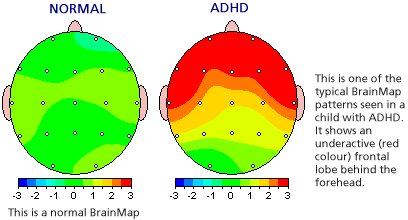

QEEG is an advance form of evaluating individual brain regions by collecting and analyzing the electrical ‘brain waves’ (e.g. frequency and amplitude) and digitally comparing the data against a database of age-matched otherwise health individuals. This brain map is a very precise evaluation that can help 1) make more precise diagnoses as each disorder often has a ‘signature’ pattern on brain map; and 2) help design treatment protocol to reverse the areas of abnormality to a normal state. In addition, brain mapping can help patients visualize the exact abnormalities and see the ‘before’ and ‘after’ results of treatment tab. Learn more from our Real Cases.